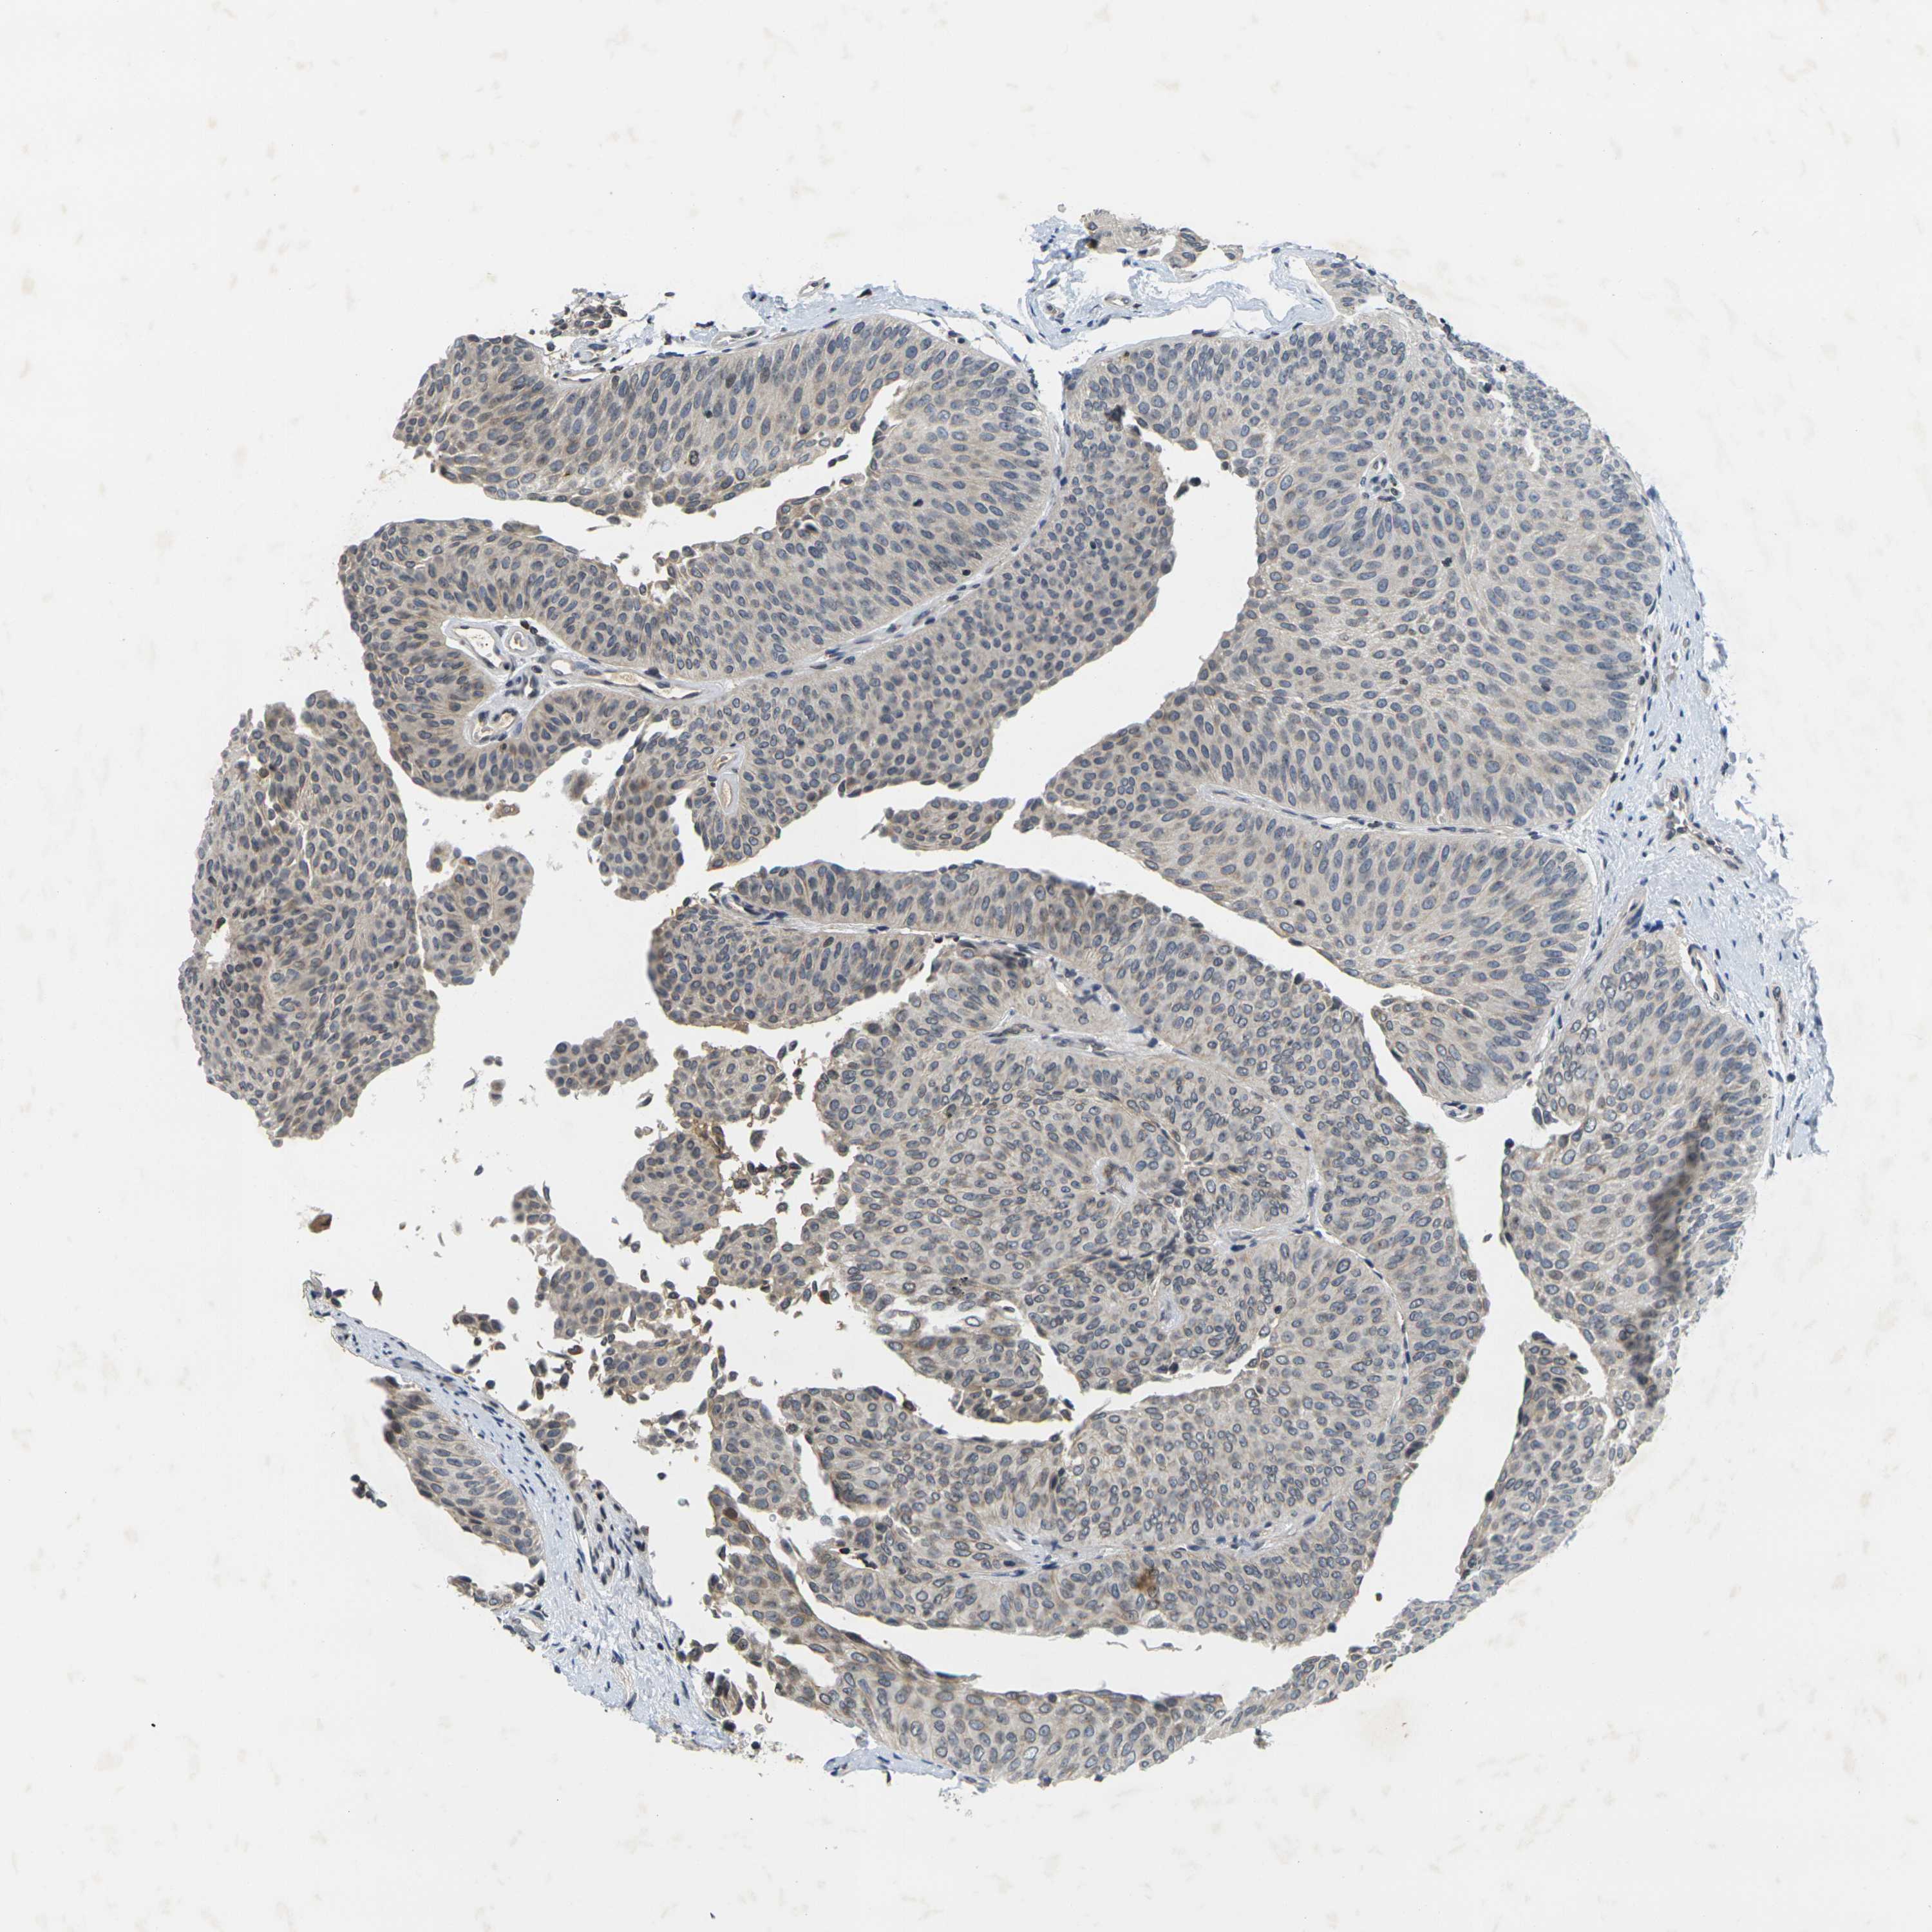

UROTHELIAL CANCER - Protein expressioni

A mouse-over function shows sample information and annotation data. Click on an image to view it in a full screen mode. Samples can be filtered based on level of antibody staining by selecting one or several of the following categories: high, medium, low and not detected. The assay and annotation is described here.

Note that samples used for immunohistochemistry by the Human Protein Atlas do not correspond to samples in the TCGA dataset.

Antibody stainingi

Antibody staining in the annotated cell types in the current human tissue is reported as not detected, low, medium, or high, based on conventional immunohistochemistry profiling in selected tissues. This score is based on the combination of the staining intensity and fraction of stained cells.

Each image is clickable and will lead to virtual microscopy that enables deeper exploration of all samples and also displays staining intensity scores, fraction scores and subcellular localization as well as patient and tissue information for each sample.

Antibody HPA001471

Antibody CAB009828

Staining

High

Medium

Low

Not detected

Intensity

Strong

Moderate

Weak

Negative

Quantity

>75%

75%-25%

<25%

None

Location

Nuclear

Cytoplasmic/membranous

Cytoplasmic/membranous,nuclear

Urothelial carcinoma, High grade

Urothelial carcinoma, Low grade

Adenocarcinoma, NOS